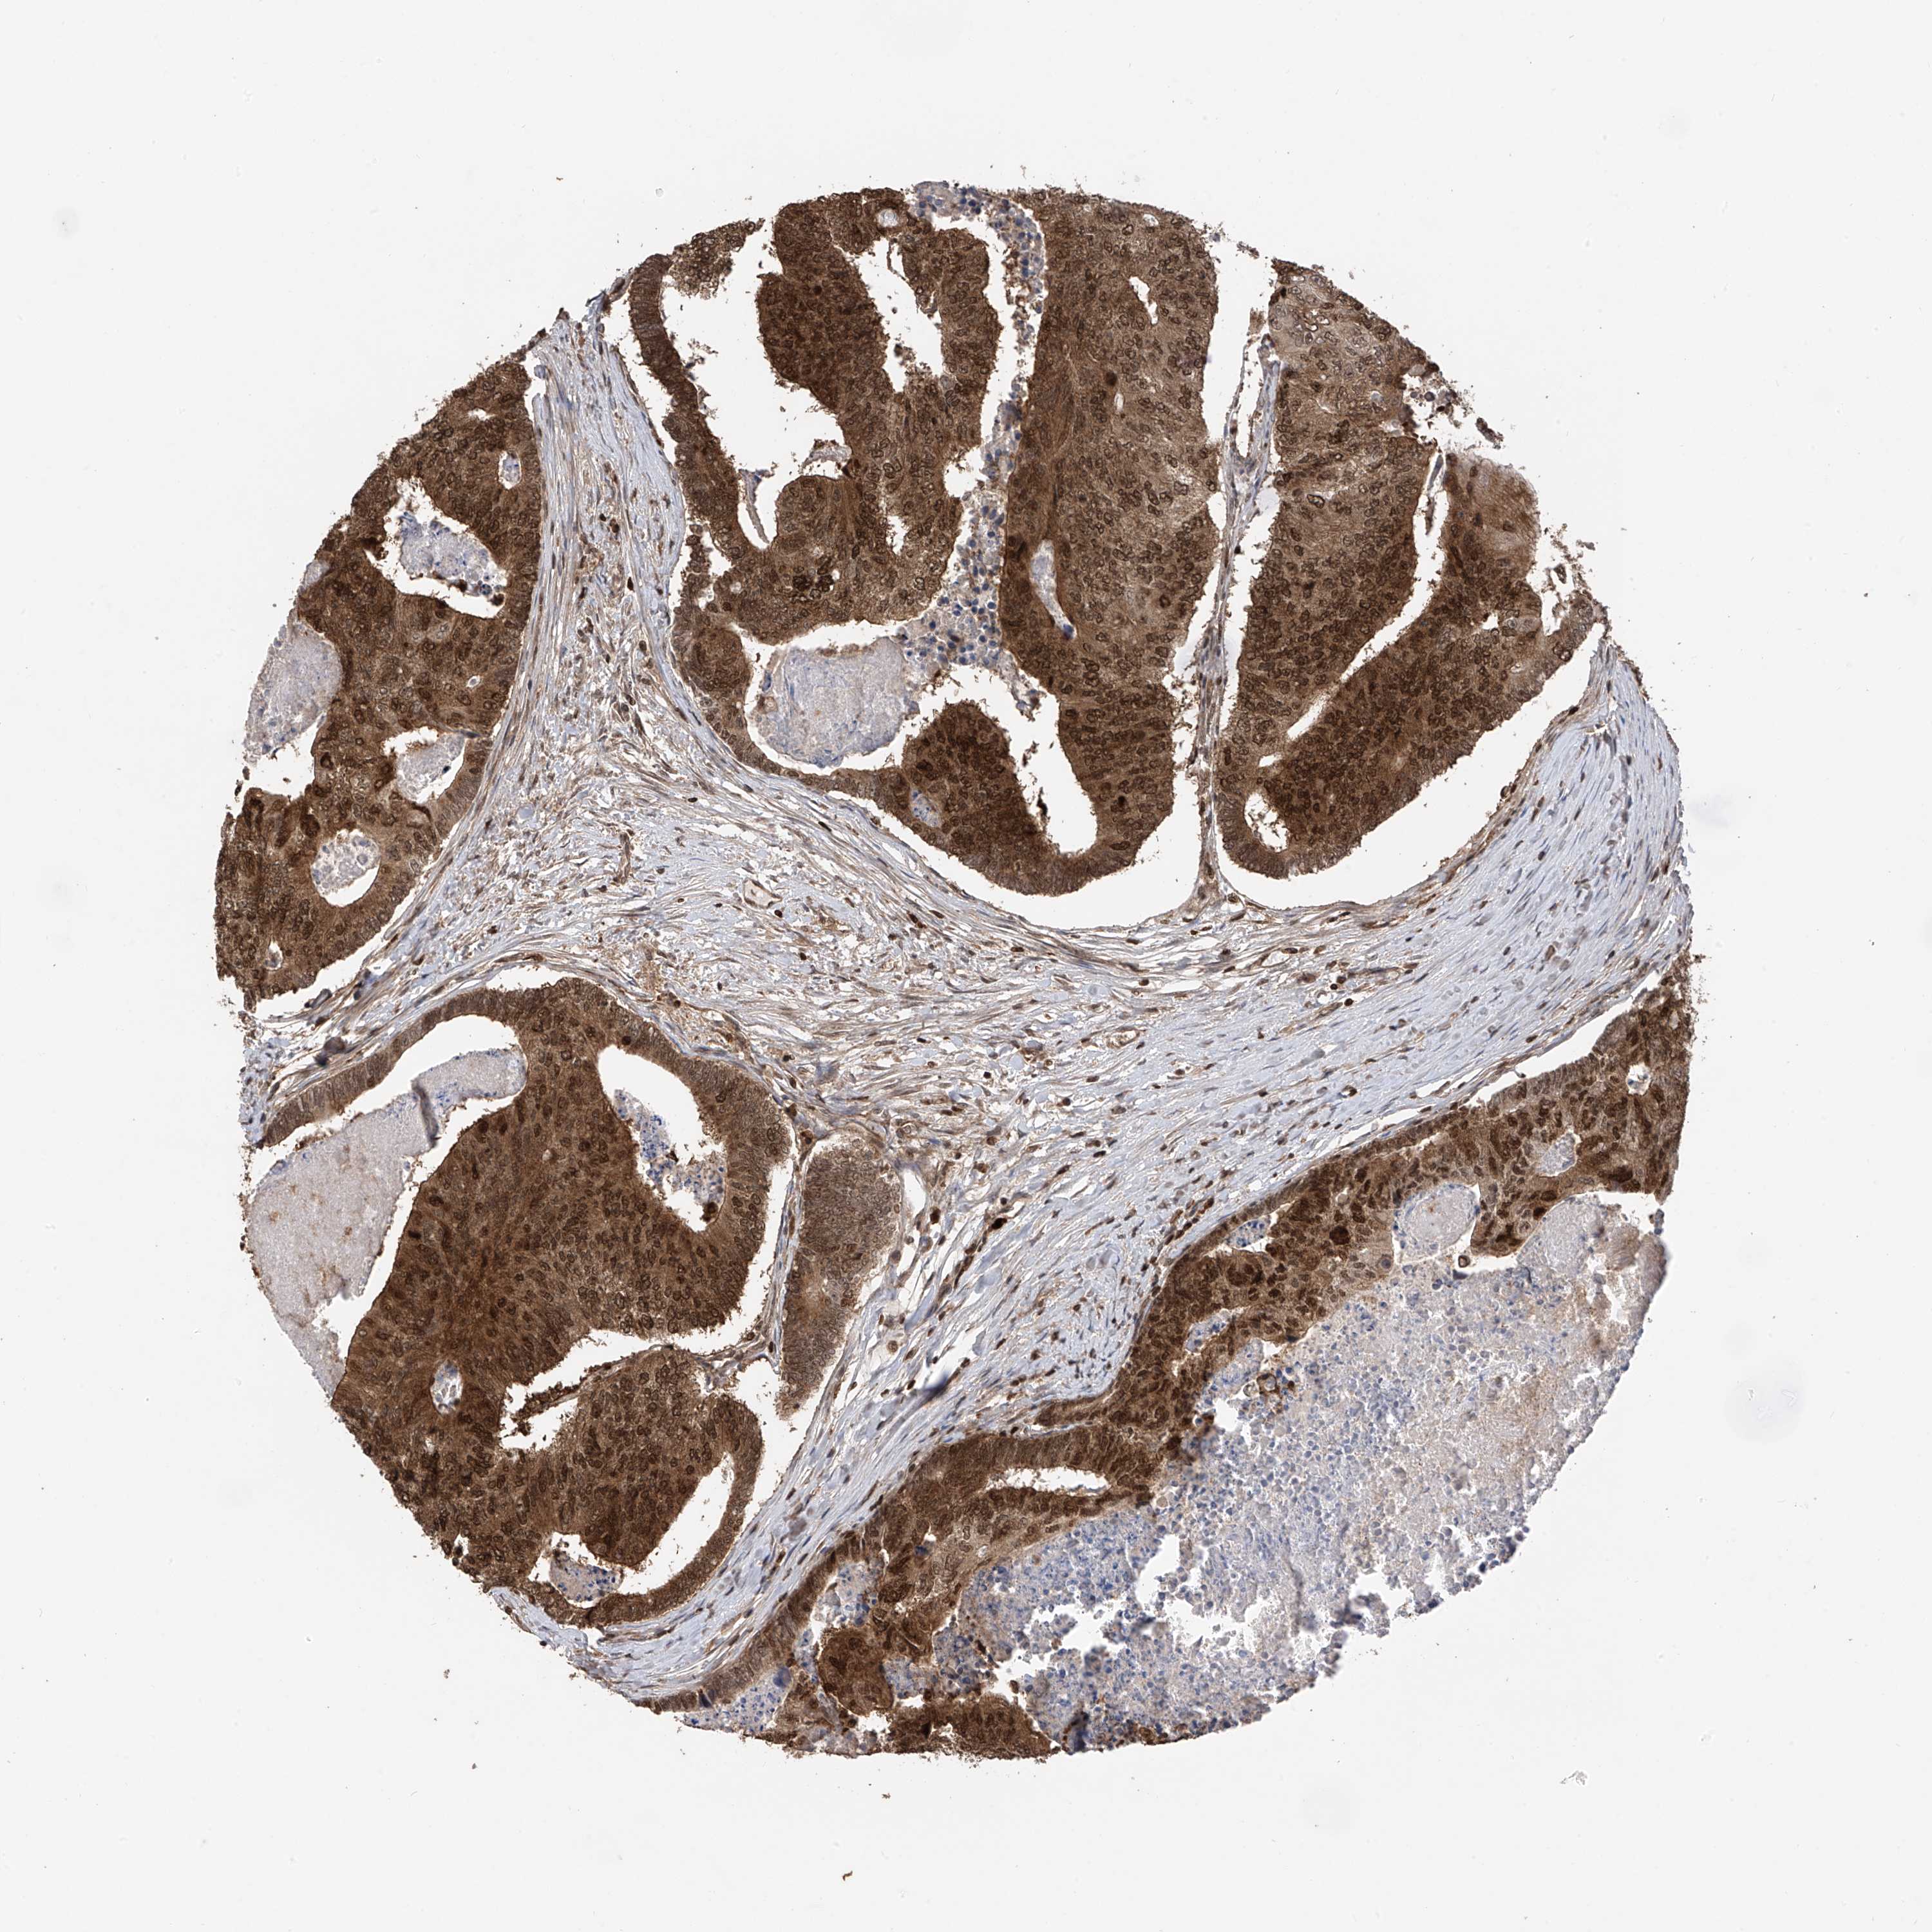

CANCER COLORECTAL CANCER Show tissue menu

Colorectal cancer

Colon adenocarcinoma